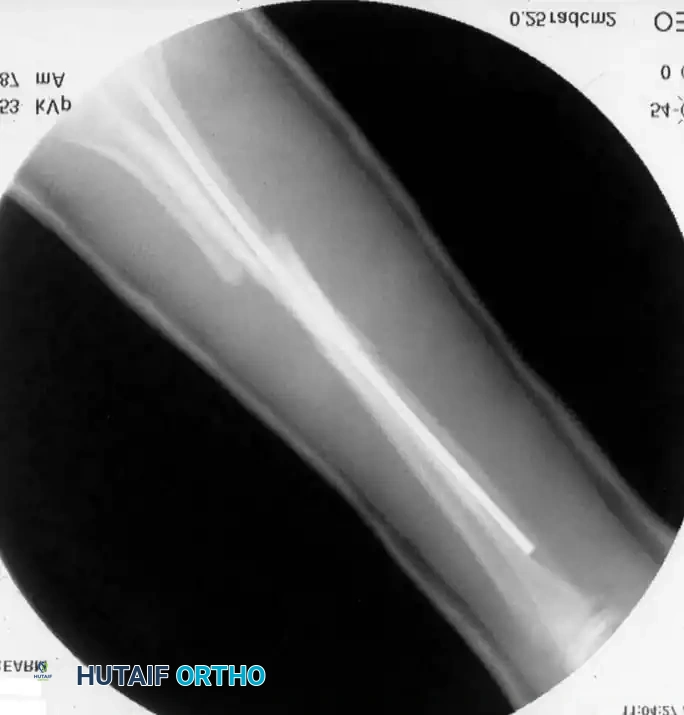

2. Elastic Stable Intramedullary Nailing (ESIN)

ESIN has become the gold standard for displaced, unstable pediatric forearm fractures. Lascombes et al. and Flynn and Waters popularized this technique, citing minimal soft-tissue dissection, preservation of the fracture hematoma, and the ability to achieve three-point biomechanical fixation.

Preoperative Planning:

Nail diameter should be approximately 40% of the narrowest intramedullary canal diameter. Titanium elastic nails (TENs) are preferred for their modulus of elasticity.

5. Final Seating: The nails are advanced to the opposite metaphyses. The trailing ends are cut, leaving 1-2 cm outside the bone but buried beneath the skin to facilitate future removal.

Image